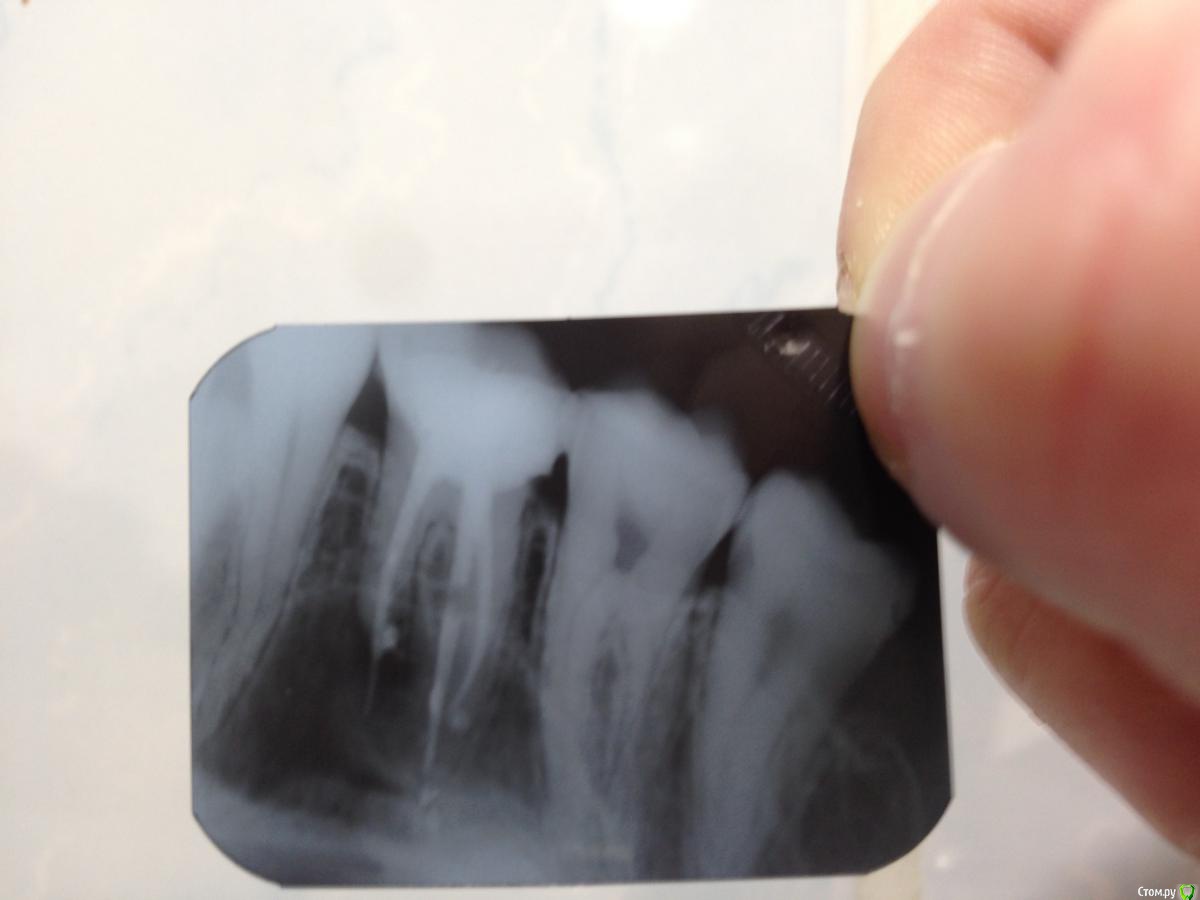

George58rus Опубликовано 12 января, 2015 Автор Поделиться Опубликовано 12 января, 2015 Скорее всего эндодонтическое лечение было несостоятельным.Необходим рентгеновский снимок зуба на сегодня.Спасибо за внимание. В эти выходные зуб довольно сильно ныл, быль боль при надкусывании в области пломбы и температура 37.4. Сегодня с утра температуры нет, боли почти нет, сходил сделал снимок. Посмотрите? Ссылка на комментарий

SDC Опубликовано 12 января, 2015 Поделиться Опубликовано 12 января, 2015 Спасибо за внимание. В эти выходные зуб довольно сильно ныл, быль боль при надкусывании в области пломбы и температура 37.4. Сегодня с утра температуры нет, боли почти нет, сходил сделал снимок. Посмотрите? Изменения воспалительного характера в области верхушки медиального корня. Корневой канал (1(!), а там должно быть 2) запломбирован с выходом пломбировочного материала за верхушку.Для продолжение он-лайн диагностики (для выявления наличия доп. к.к. в м.б. корне этого зуба) необходимо сделать компьютерную томограмму, архивировать исследование и выложить на облако для скачивания.Необходимость в ревизии корневых каналов есть, поэтому второй вариант - записаться на прием к доктору эндодонтисту (специалист по лечению к.к.) и начать перелечивание к.к. (всех или только 2-х в м.б. корне) - это определить Ваш Док.Затем протезирование коронкой. 1 Ссылка на комментарий

IvanK Опубликовано 12 января, 2015 Поделиться Опубликовано 12 января, 2015 мне кажется и с пломбой проблемы, возможно зуб очень глубоко разрушен.... похоже на танцы с бубном.. 1 Ссылка на комментарий